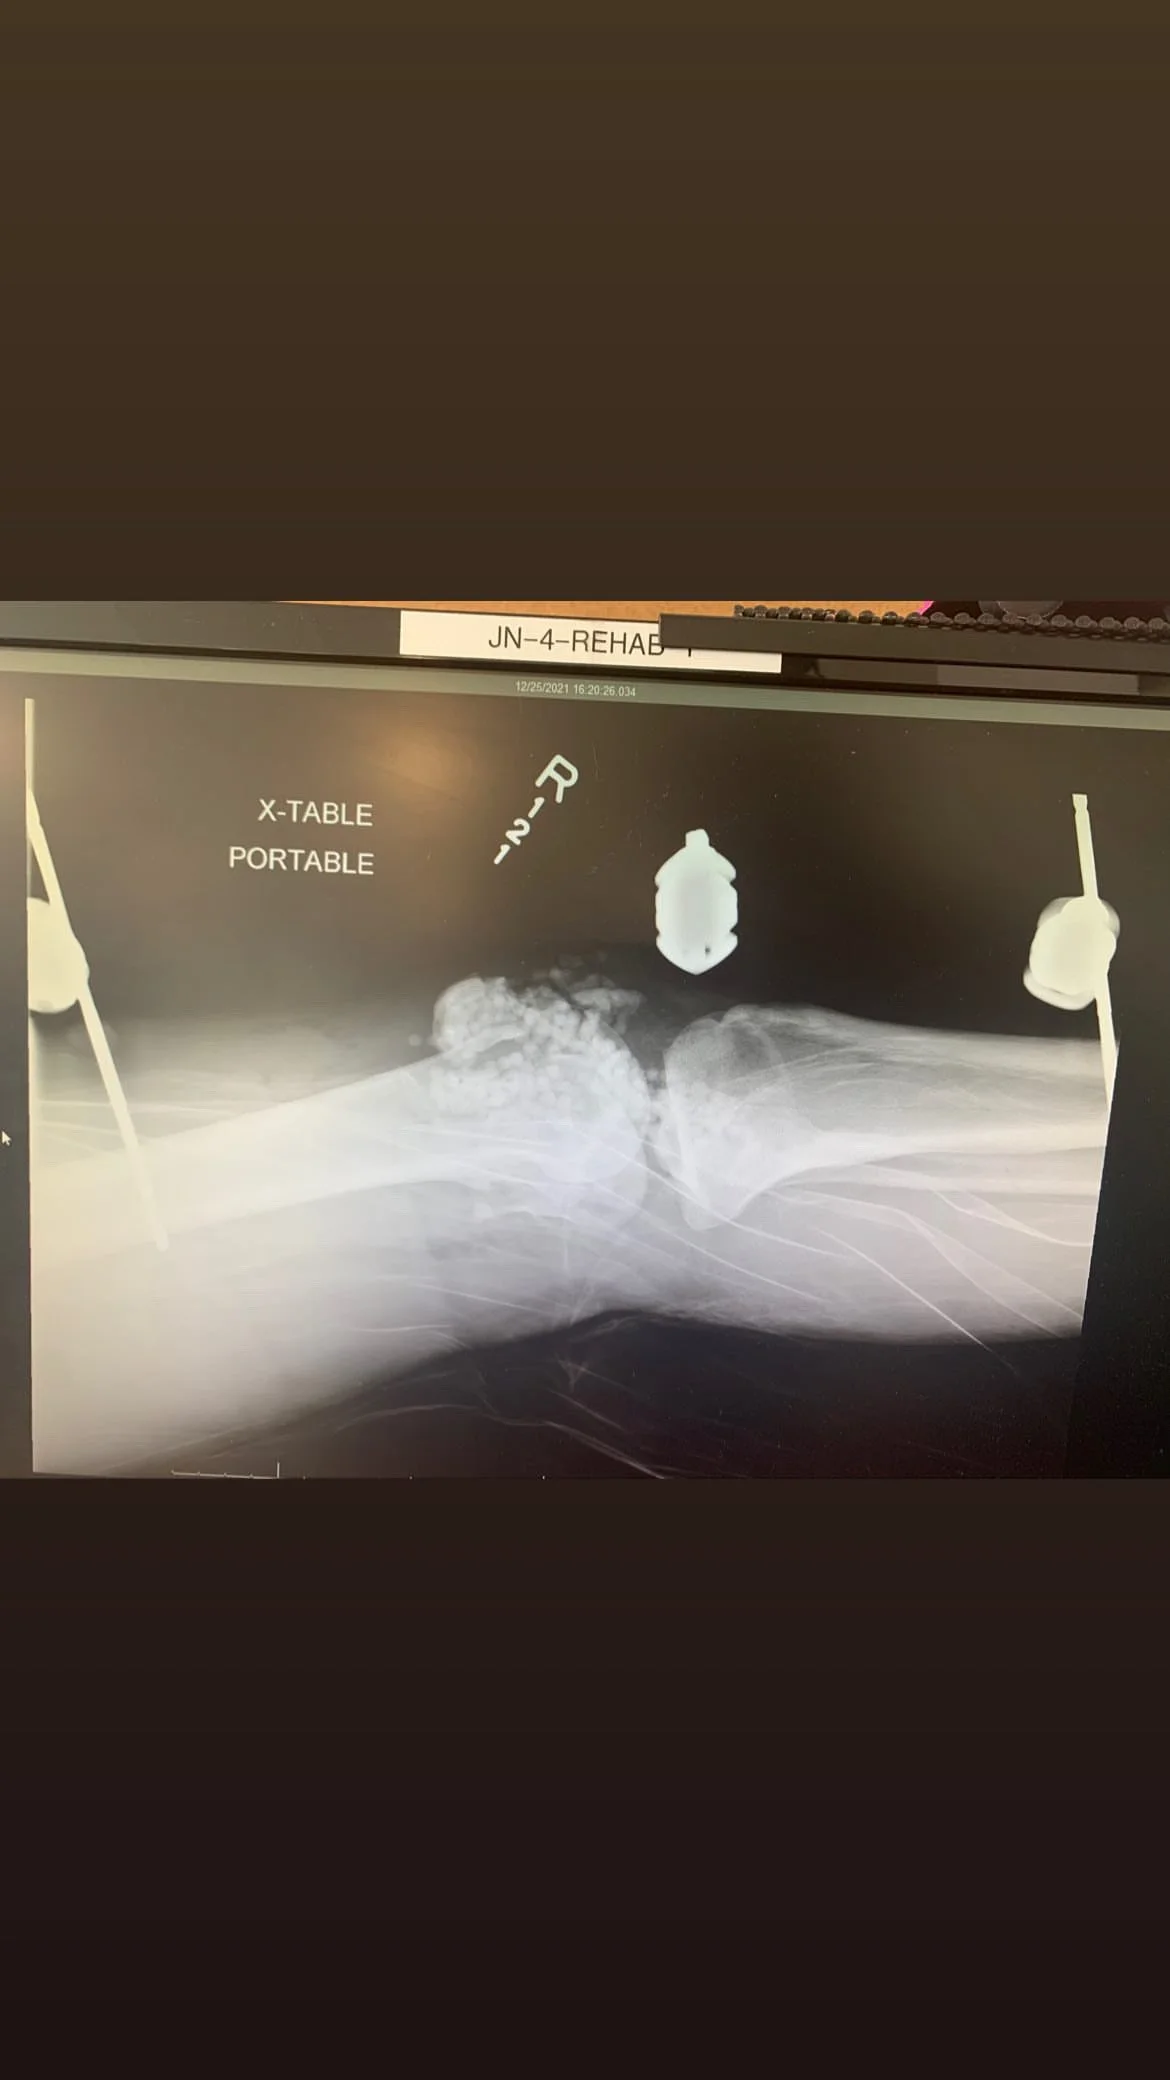

After a serious car crash, Tad suffered severe lacerations to his internal organs, complete breaks in his right arm, and total destruction of his right knee.